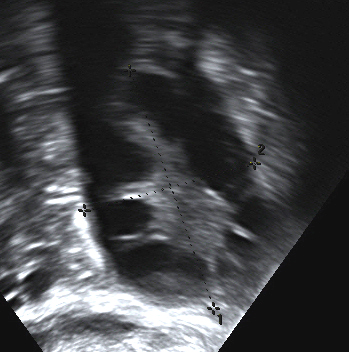

Ultrasound may not be required to make the diagnosis, but if you are doing it transvaginal ultrasound is best.